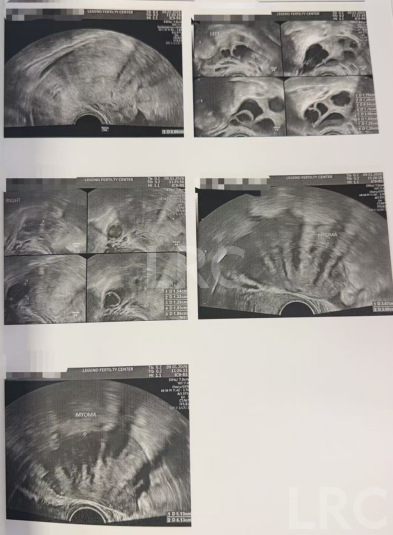

月经第二天 促排第一天

阴超检查:基础卵泡 14 颗

- 右侧卵泡 5 颗 (7,6,5,5,5mm)

- 左侧卵泡 9 颗 (7,6,6,6,6,5,5,5,5mm)

激素水平检查:

- 促黄体生成素 5.60 miu/ml

- 雌二醇 42.90 pg/ml

- 促卵泡生成素 7.60 miu/ml

- 泌乳素 9.30 miu/L

促排第六天

阴超检查(只数能用卵子):

- 右侧卵泡 6 颗 (14,11,9,9,8mm)

- 左侧卵泡 5 颗 (14,14,13,11,11mm)

- 促黄体生成素 3.60 miu/ml

- 雌二醇 313 pg/ml

促排第八天

阴超检查:

- 右侧卵泡 4 颗 (17,14,14,13mm)

- 左侧卵泡 5 颗 (17,16,16,15,15,13mm)

子宫内膜厚度:6.6 mm

促排第十天

- 右侧卵泡 4 颗 (18,18,16,13mm)

- 左侧卵泡 6 颗 (22,21,20,20,17,13mm)

子宫内膜厚度:10.2 mm